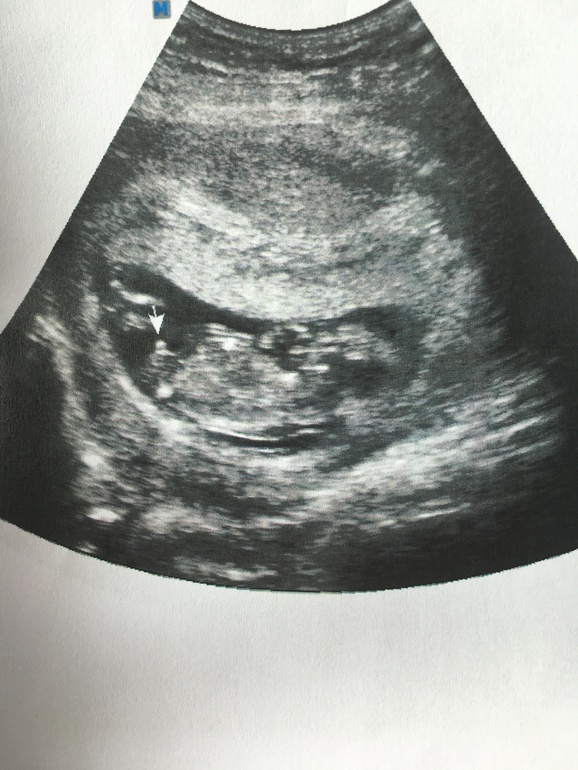

Пол малышаДевочки , посмотрите пожалуйста, тут прям точно мальчик ? Не изменится уже ничего? Пол сказали в цир, Мучаидзе . Причём даже без :" даю столько- то процентов". Просто сказала : у вас мальчик . Эх, так дочку хотелось . Понимаю, что в 12 недель ( на момент узи 12,5 ) ошибок много , но тут так торчит (( наверное, не надо и надеятся на банты ?

Мне Мучаидзе ни в 11,3 , ни в 12,5 не ошиблась оба раза, хотя я до родов сомневалась. Но она говорит, что никогда пол не озвучивает, если не уверена. Ну а в вашем случае мне кажется 100 % мальчишка судя по фото. Вообще говорят, что мальчика могут принять за девочку на раннем сроке, а наоборот у хорошего специалиста почти никогда.

Вообще фото довольно таки размытое и вместе с этим кружочком есть ещё кружочек ниже, а если это просто шумы так легли?

Я бы пока не доверяла этому. Во первых окончательно половые органы разовьются к 14 неделе и сейчас это всего лишь предположения. По крайне мере в книжке про беременность пишут до 14 недели пол не определить. У кого-то может и совпало с тем что показалось узисту, а может и не совпасть. Так что все решит второй скрининг ;)

Если Екатерина сказала что мальчик, значит мальчик, надежд нет. Я у Мучаидзе все беременности делаю узи, она обычно в 11 нед уже говорит кто там , ни разу не ошиблась не мне, ни моим друзьям